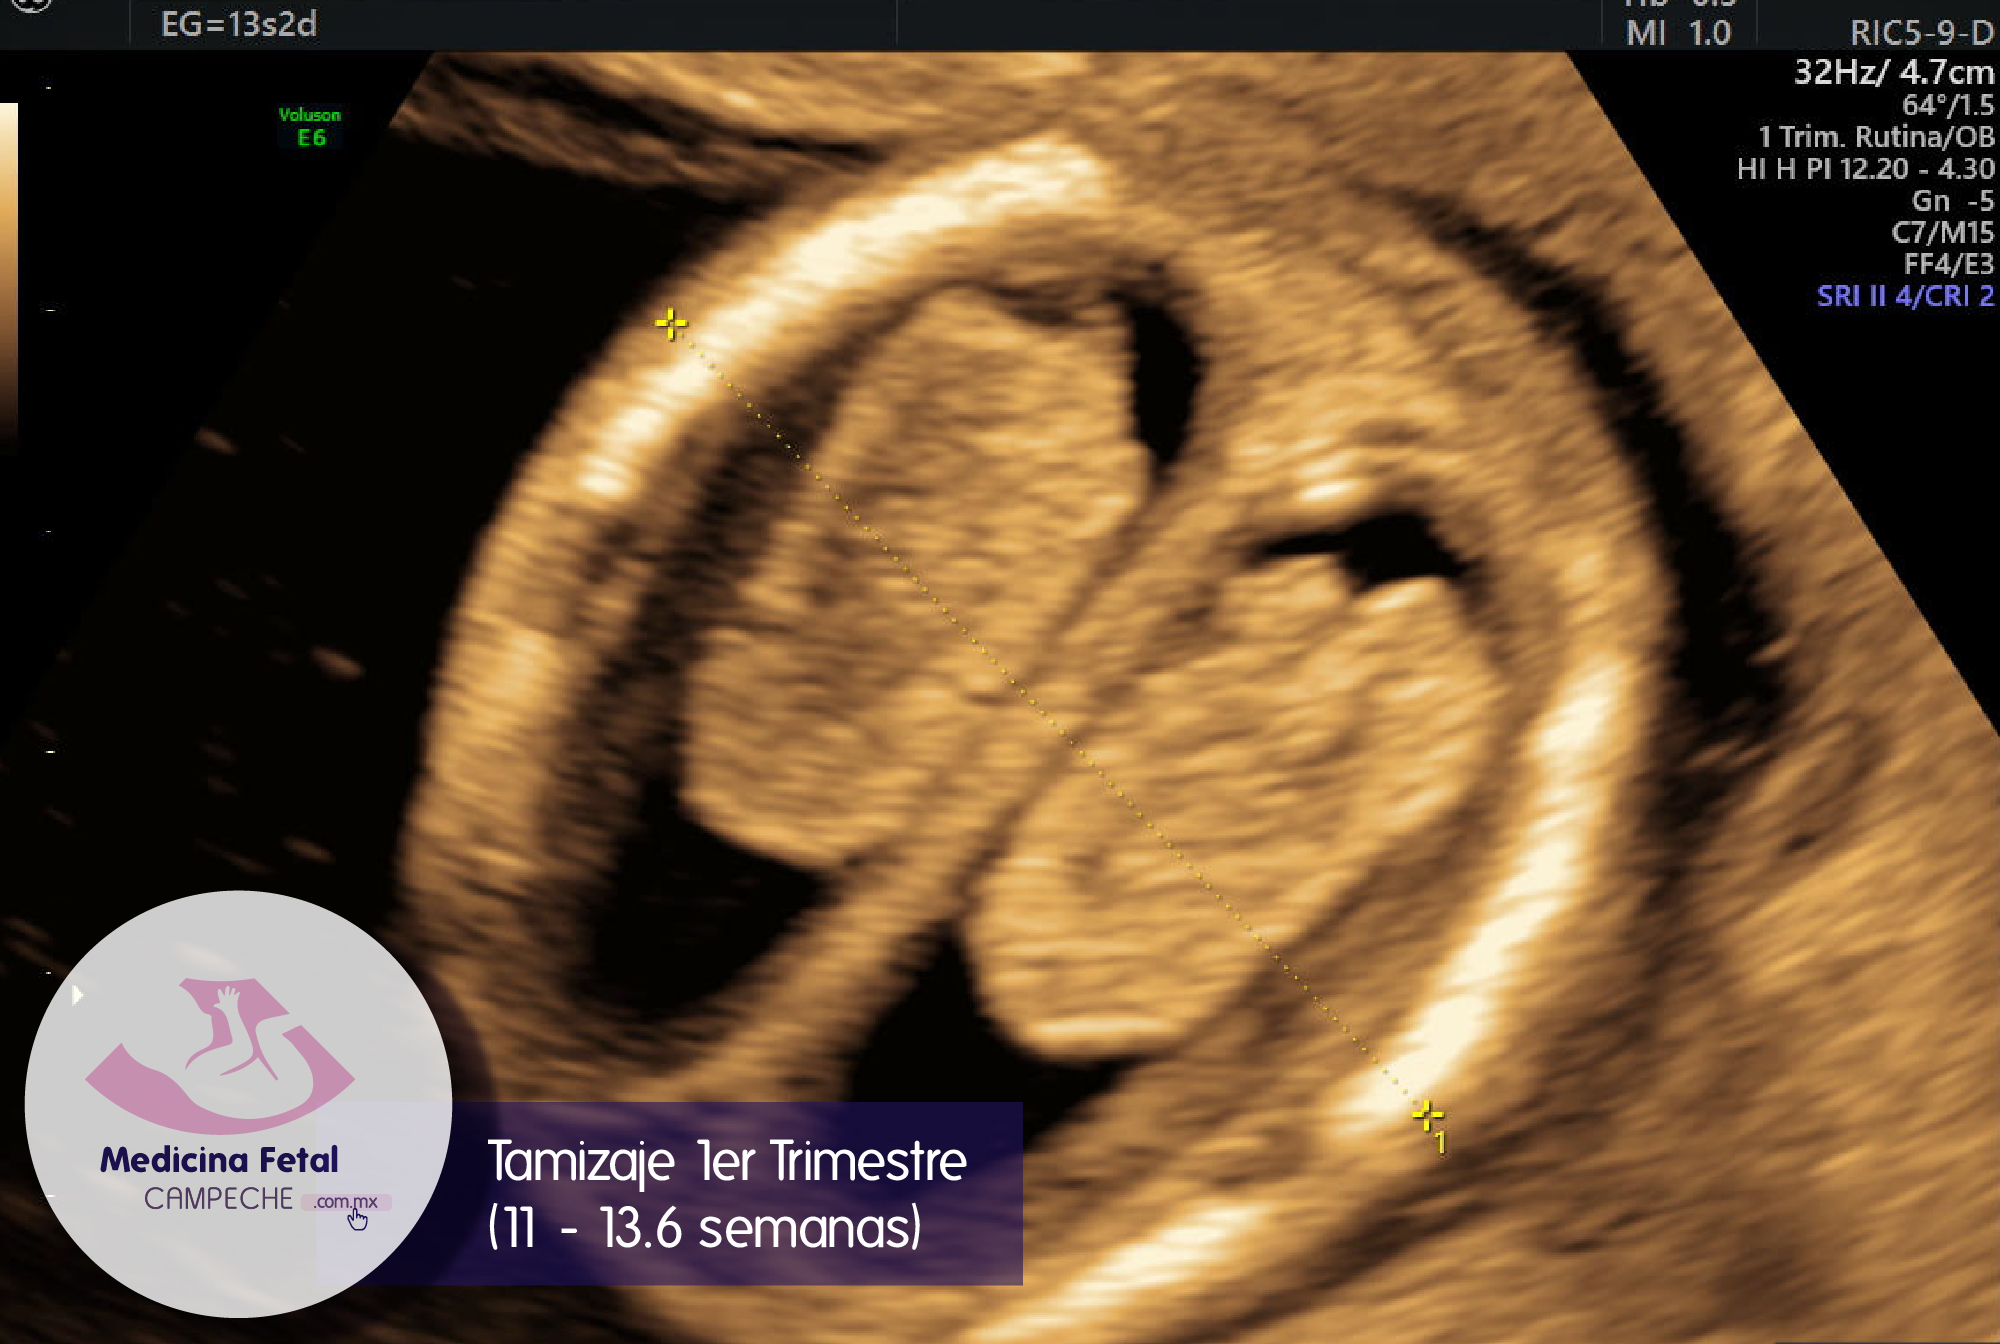

El más recomendado es el tamizaje combinado: en el que utilizamos marcadores obtenidos por ultrasonido y marcadores bioquímicos (en sangre); es el estudio que nos da la más alta taza de detección de trisomías y preeclampsia.

El tamizaje ultrasonográfico: en el que sólo utilizamos marcadores obtenidos por ultrasonido; en este estudio la taza de detección es menor que con el combinado.

Utilizamos estándares y normas internacionales para darte una mayor certeza diagnostica y, el cálculo de riesgo lo realizamos mediante el algoritmo diseñado por la Fetal Medicine Foundation de Londres Inglaterra, organismo rector a nivel mundial en el tamizaje del primer trimestre del embarazo. Somos médicos certificados por este instituto, requisito indispensable para poder tener el acceso al Software correspondiente.